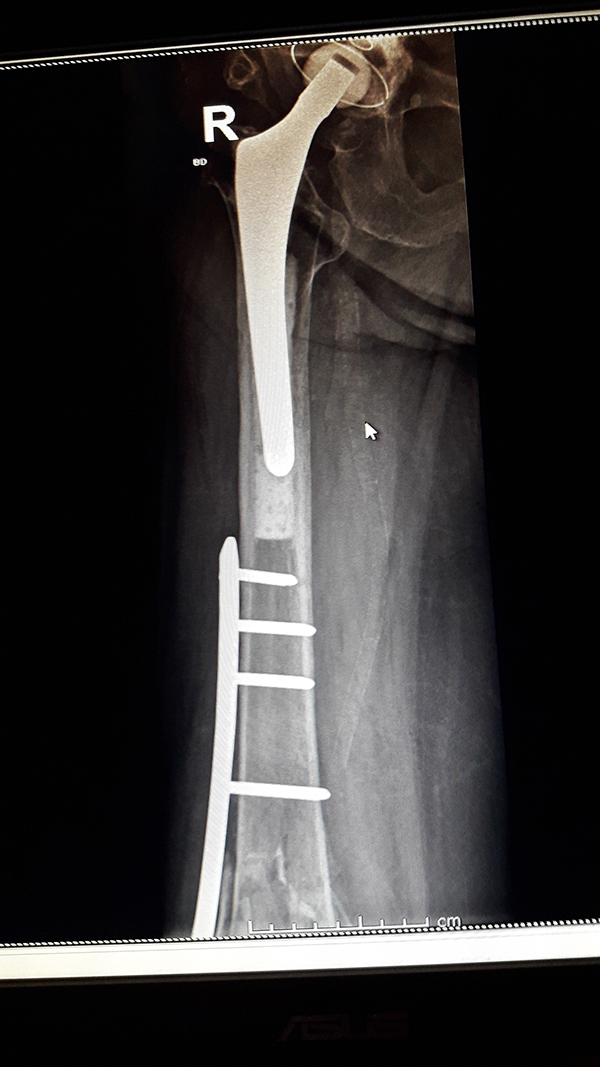

Miednica i kończyna dolna